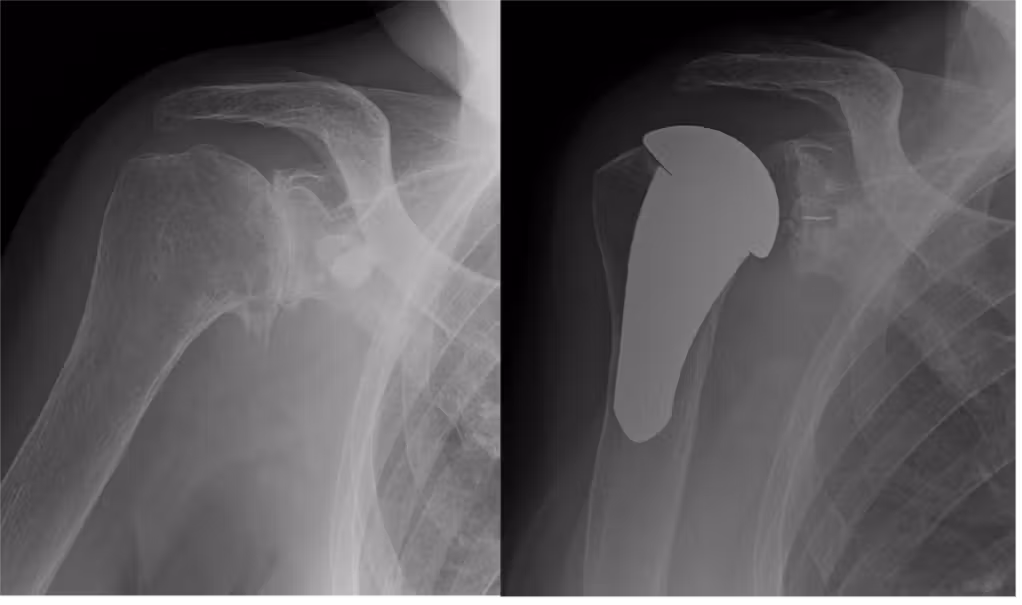

上肢人工関節は下肢関節とは違い体重のかからない関節ですので、痛みをとるだけではなく関節の動きを改善し、関節の機能をよくする目的で手術を行っております。関節軟骨が破壊された部位を切除し人工関節に置き換えます。腱板の機能が温存されている場合は、解剖学的な人工関節を選択し、腱板機能不全の患者様に対しては反転型の人工肩関節を用い機能改善を目指しております。

変形性肩関節症に対する人工肩関節置換術(解剖型)